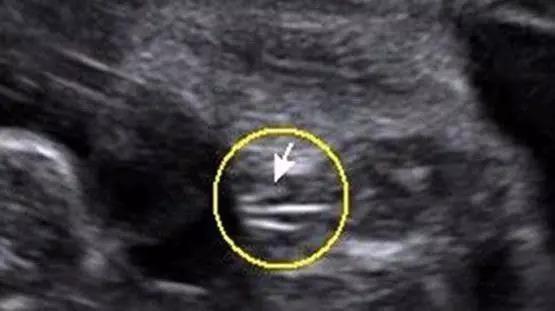

四维彩超怎么看性别?别人是不会说的

女宝b超双腿间有圆球

四维看男女器官